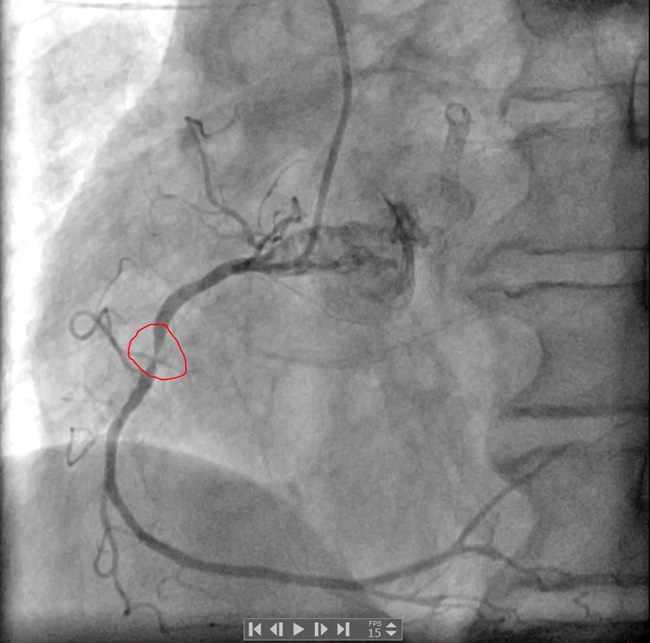

冠脉造影结果显示:左主干未见明显异常,前降支近中段可见支架影,近段支架内狭窄50%,前向血流TIMI3级;回旋支近段次全闭塞,前向血流TIMI2-3级;右冠中段弥漫性狭窄,最重处狭窄95%,前向血流TIMI3级。

最终由手术医师为买买提做了介入治疗:右冠置入支架1枚,回旋支置入药物球囊1枚。